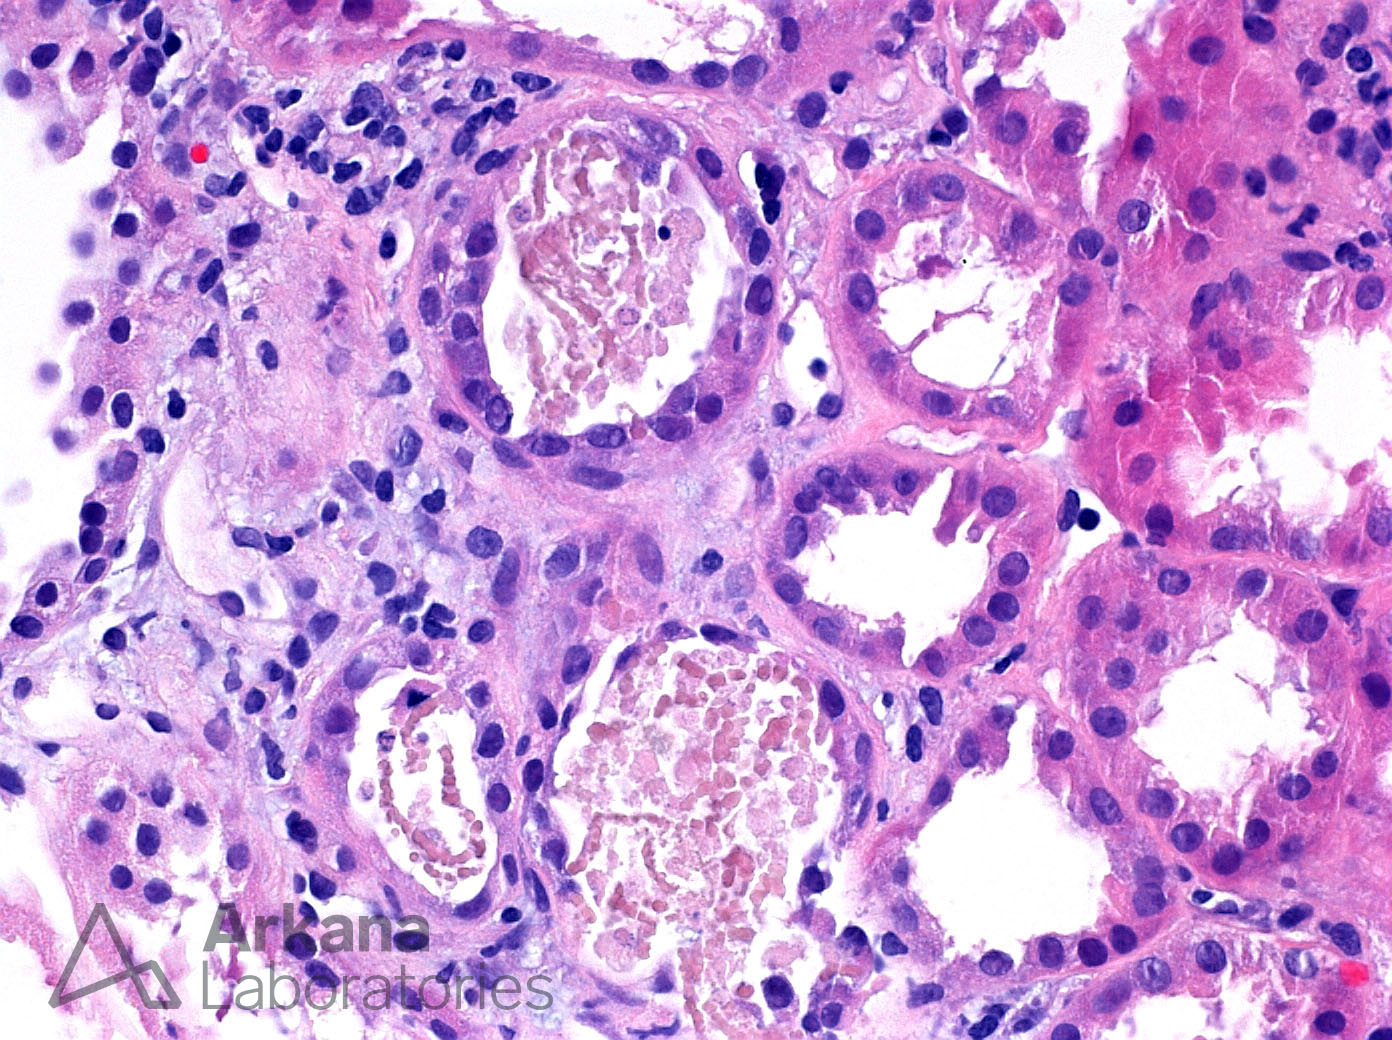

Pigmented Myoglobin Cast on H&E